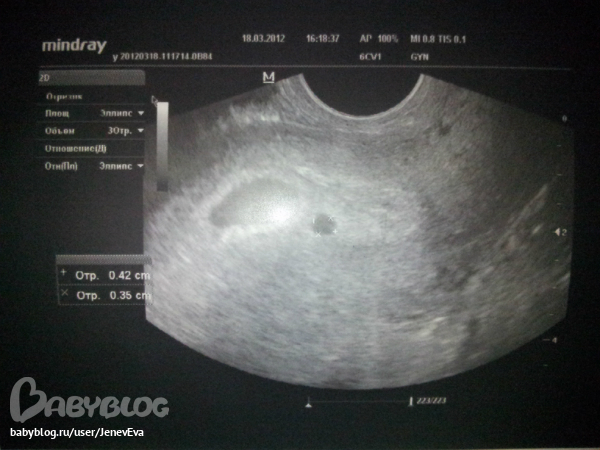

Может кто сталкивался с такими вот картинами на узи? Врач поставила диагноз что отслоение какое-то, но так же сказала что может быть и многоплодная была но один плод стал развиваться а второй нет. вот сижу и плачу ;(

а их могло бы быть и два(